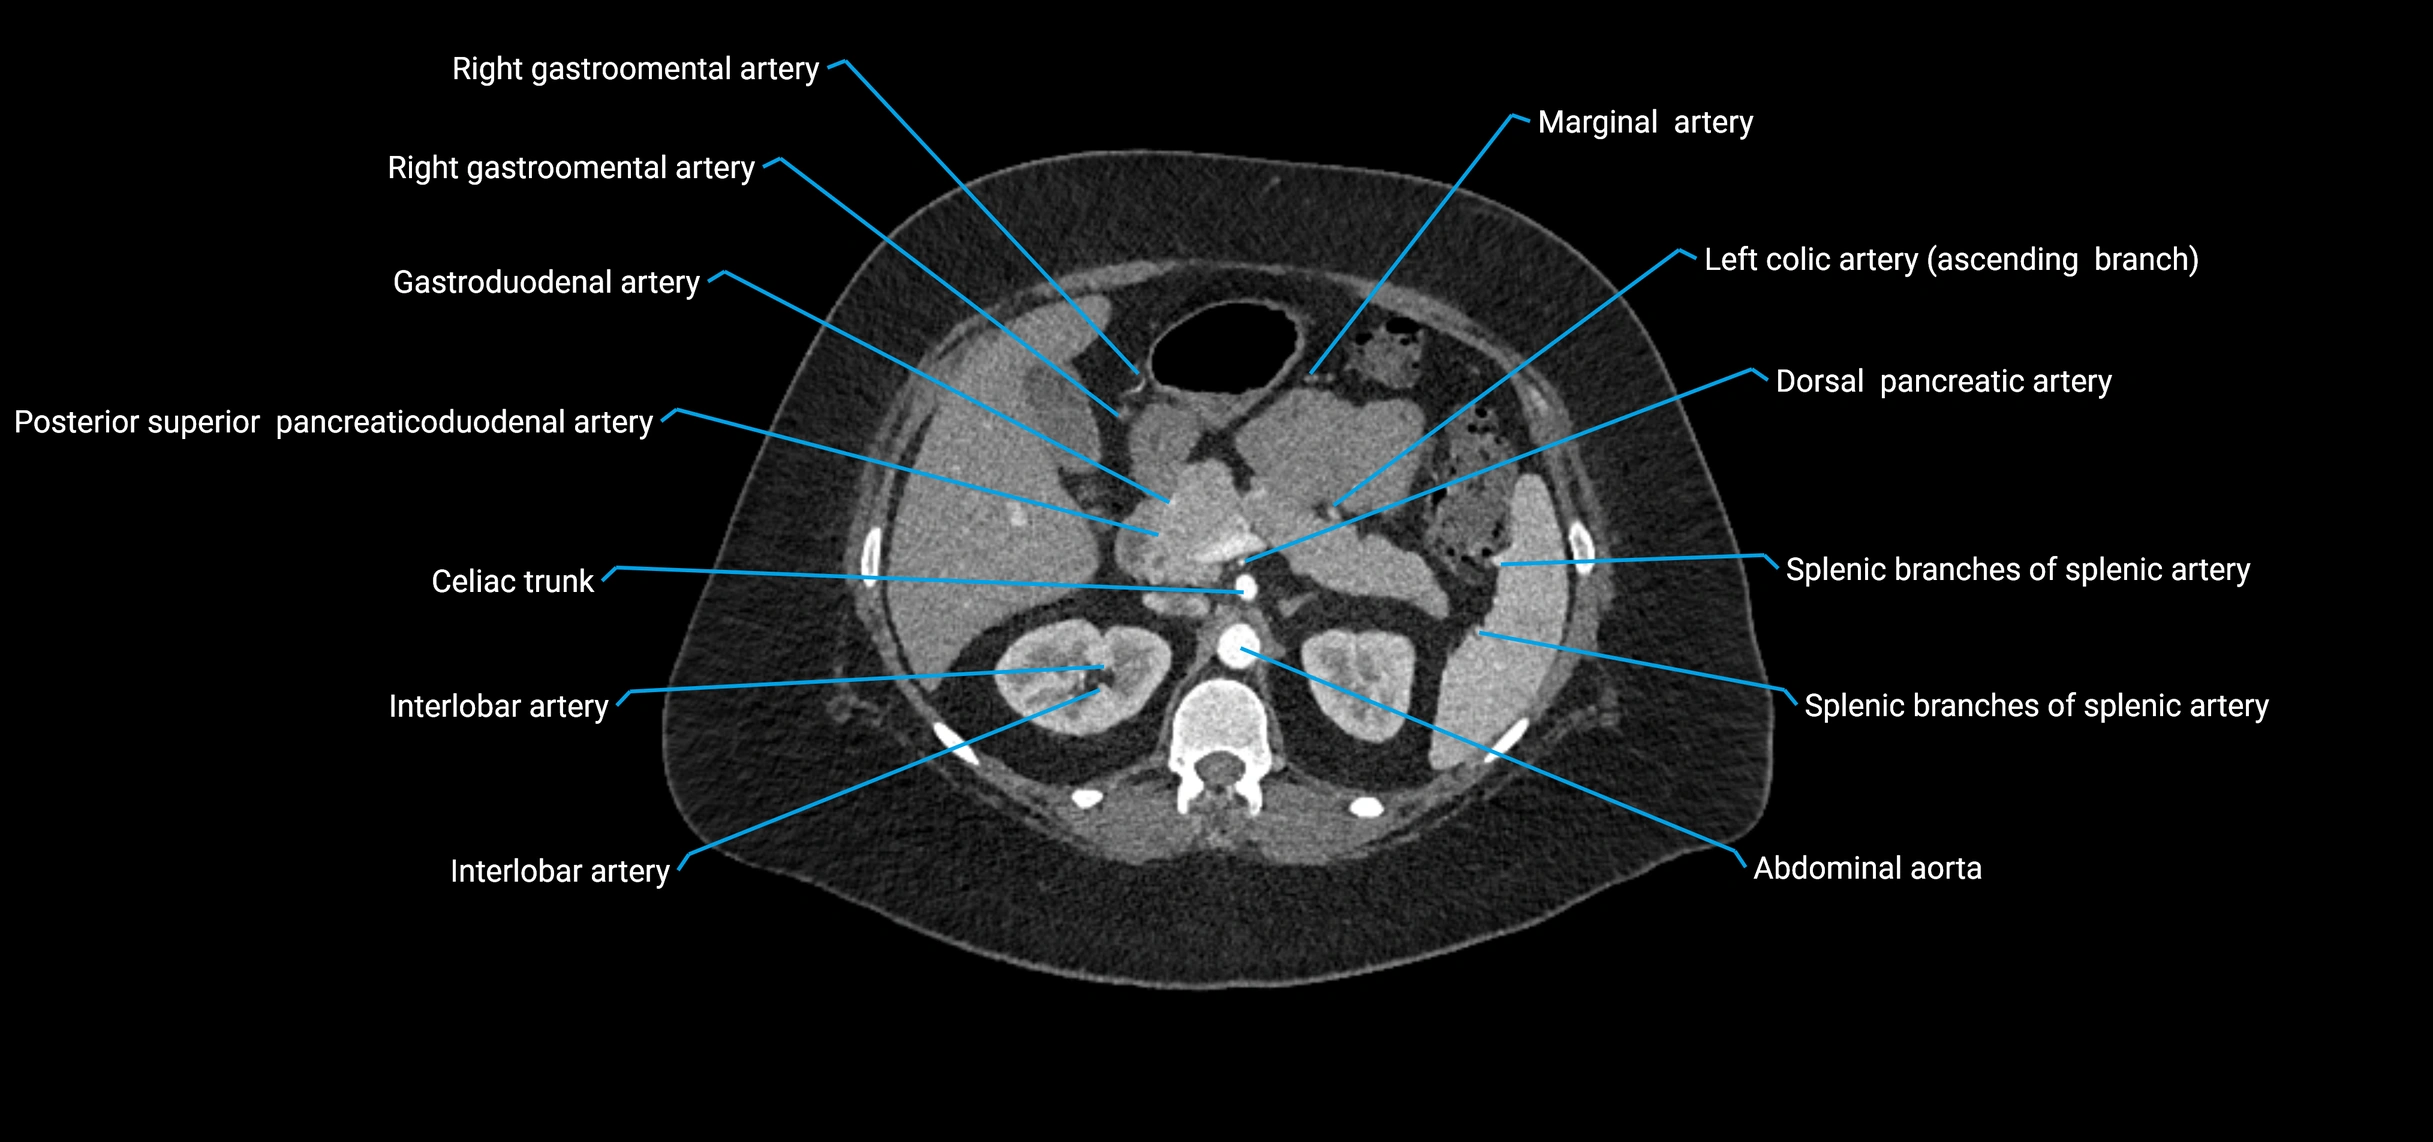

CT images

image

Contrast-enhanced CT (CTA):

• Gold standard for abdominal aortic imaging

• Provides excellent detail of lumen, wall, aneurysm, thrombus, and branch vessels

• Multiplanar and 3D reconstructions help in aneurysm measurement, stent graft planning, and dissection evaluation